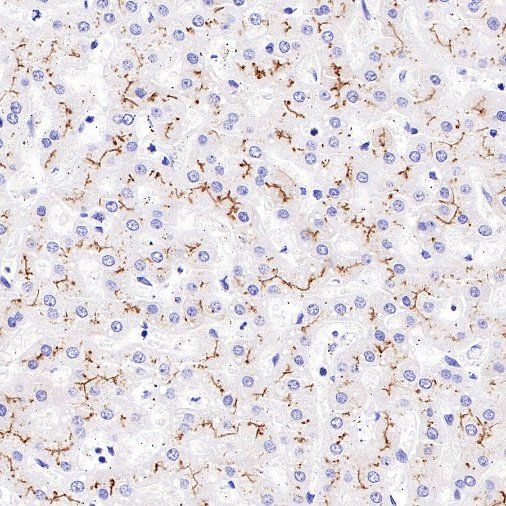

Immunohistochemistry

IHC shows positive staining in paraffin-embedded human kidney. Anti-MDR1/ABCB1 antibody was used at 1/1000 dilution, followed by a HRP Polymer for Mouse & Rabbit IgG (ready to use). Counterstained with hematoxylin. Heat mediated antigen retrieval with Tris/EDTA buffer pH9.0 was performed before commencing with IHC staining protocol.